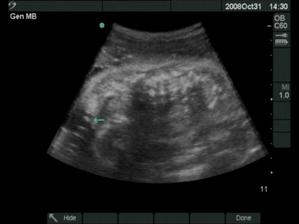

18.12.2008 prišli na svet o 3 týždne skôr naše krásne dvojičky. Ako prvá predrala cestu svojmu bratčekovi Laura, ktorá išla hlavičkou. Prišla na svet 12:53 a vážila 2720 g a merala 46 cm. Marko mal výjsť hneď na to zadočkom, ale keď zistil že sa mu uvoľnilo miesto asi si to rozmyslel a rozhodol sa v brušku zostať a spriečil sa. Pán doktor ho musel síce trochu povykrúcať aby ho dostal von, ale našťastie sa mu to podarilo a nemuseli maminu po normálnom pôrode aj rezať 🙂 Svetlo sveta uzrel Marko 13:03 a vážil 2890 g a meral 48 cm.